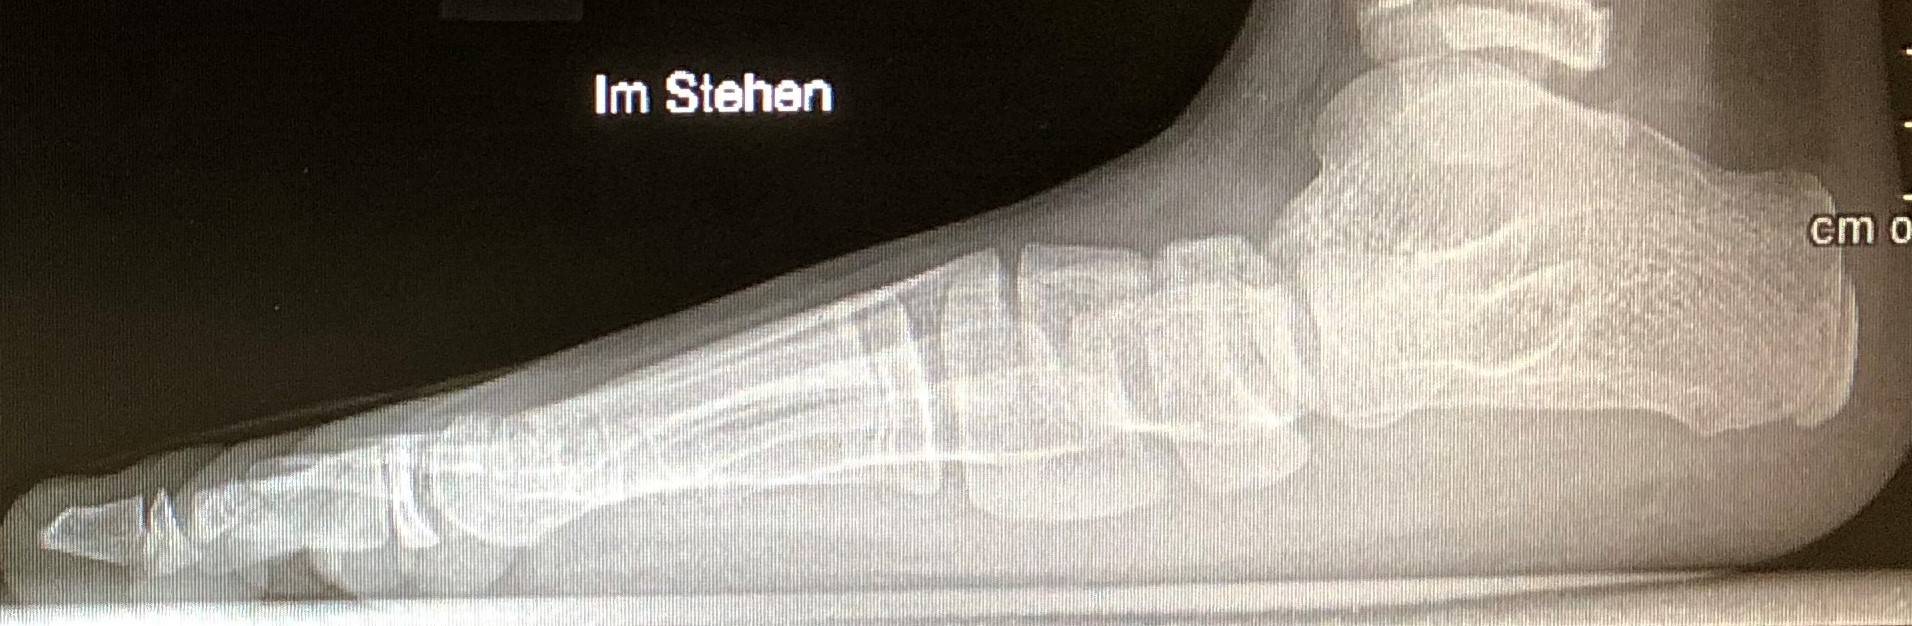

Dies bezeichnet die abflachung des fußlängsgewölbes. Beim knicksenkfuß (pes planovalgus) ist es wichtig, zwischen einer harmlosen, nicht krankhaften (physiologischen) fußdeformation bei kleinkindern und der krankhaften (pathologischen) form bei. Von einem senkfuß oder knicksenkfuß spricht man, wenn das längsgewölbe des fußes abgeflacht ist. Der kindliche knicksenkfuß stellt beim säugling und kleinkind eine normalform des fußes dar. Ich habe seit dem kindesalter jedes jahr neue schuheinlagen, nur seit ca.

Der kindliche knicksenkfuß stellt beim säugling und kleinkind eine normalform des fußes dar. Meanings of knicksenkfuß with other terms in english german dictionary : Aus dessen befund ergibt sich: Wenn das längsgewölbe des fußes (die wölbung der fußsohle an der fußinnenseite vor dem vorfußballen) abgeflacht ist, wird dies als senkfuß bezeichnet. Zwischen den zwei begriffen gibt es keine klare abgrenzung.

Siegfried schenk, fussspezialist (1070 wien, mariahilferstr.76/4/40). Ich habe seit dem kindesalter jedes jahr neue schuheinlagen, nur seit ca. Aus dessen befund ergibt sich: Daher auch die bezeichnung knicksenkfuß. Zwischen den zwei begriffen gibt es keine klare abgrenzung. Das fettpolster im bereich des sich später entwickelnden längsgewölbes ist beim säugling stark. Der kindliche knicksenkfuß stellt beim säugling und kleinkind eine normalform des fußes dar. Plattfuss oder knicksenkfuss bezeichnen die gleiche fussfehlstellung. Der knicksenkfuß, diagnose und möglichkeiten in der therapie. Klinik, pathomechanik und behandlungsoptionen | zusammenfassung die. Wenn das längsgewölbe des fußes (die wölbung der fußsohle an der fußinnenseite vor dem vorfußballen) abgeflacht ist, wird dies als senkfuß bezeichnet. Hat, von hinten betrachtet, die ferse zusätzlich einen „knick spricht man von einem knicksenkfuß. Wo genau die grenze zwischen diesen beiden fehlstellungen ist, ist noch unklar.